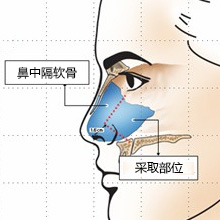

鼻中隔软骨鼻尖延长与立体

鼻中隔软骨鼻尖延长与立体鼻中隔软骨是两个鼻道中起分割作用的板状软骨,取材部位与鼻整形处于同一术野,不用另外开刀,避免了异体组织排异反应,性高。

用鼻中隔软骨与耳软骨综合塑造鼻尖,恰到好处地弥补了传统单纯采用耳软骨或自体软骨塑造的缺陷,将两种材料有机结合使用,优缺点互补,同时通过鼻部左右软骨的顶部与鼻尖上区转折点、鼻小柱-小叶角构成的四个点位进行鼻尖微调,将鼻尖部皮肤支撑到较为的角度,这样会让鼻尖更稳固、更,且看起来饱满圆润,生动娇俏不生硬,塑造出的鼻尖玲珑有致!